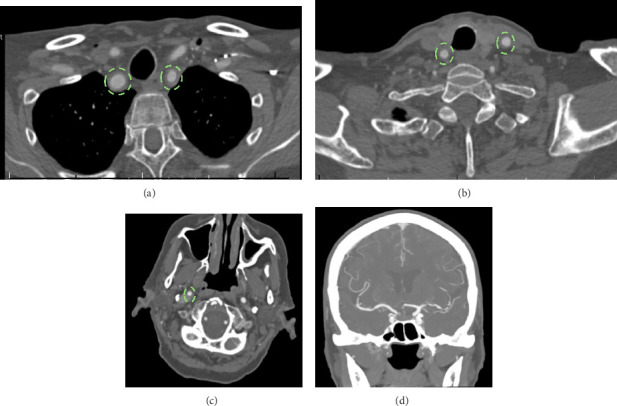

Giant cell arteritis (GCA) is an inflammatory vasculitis affecting large and medium-sized arteries, leading to complications such as arterial dissection, blindness, and stroke. Rarely, GCA presents with Horner's syndrome due to sympathetic neuron involvement from arterial inflammation. This case report discusses an 82-year-old female with hypertension, atrial fibrillation, and arthritis who presented with a 24 h history of right eye ptosis, blurred vision, dizziness, and aching eye pain. She had a mild headache and tenderness over the right temporomandibular joint but no temporal artery tenderness. Examination revealed right eye ptosis and miosis, indicative of Horner's syndrome, with no other neurological deficits. Lab results showed elevated ESR (68 mm/h) and CRP (16 mg/L). MRI with contrast revealed mild to moderate stenosis and enhancement in bilateral MCAs and basilar artery with inflammation in the right distal extracranial ICA, suggesting an inflammatory process. The patient was started on prednisone 40 mg daily. A temporal artery biopsy confirmed GCA with characteristic histopathological findings. Her prednisone dosage was increased to 60 mg/day, and she was started on tocilizumab. This case underscores the need to consider GCA in patients with Horner's syndrome and the importance of vessel wall imaging, as early corticosteroid treatment can prevent complications like vision loss and stroke.